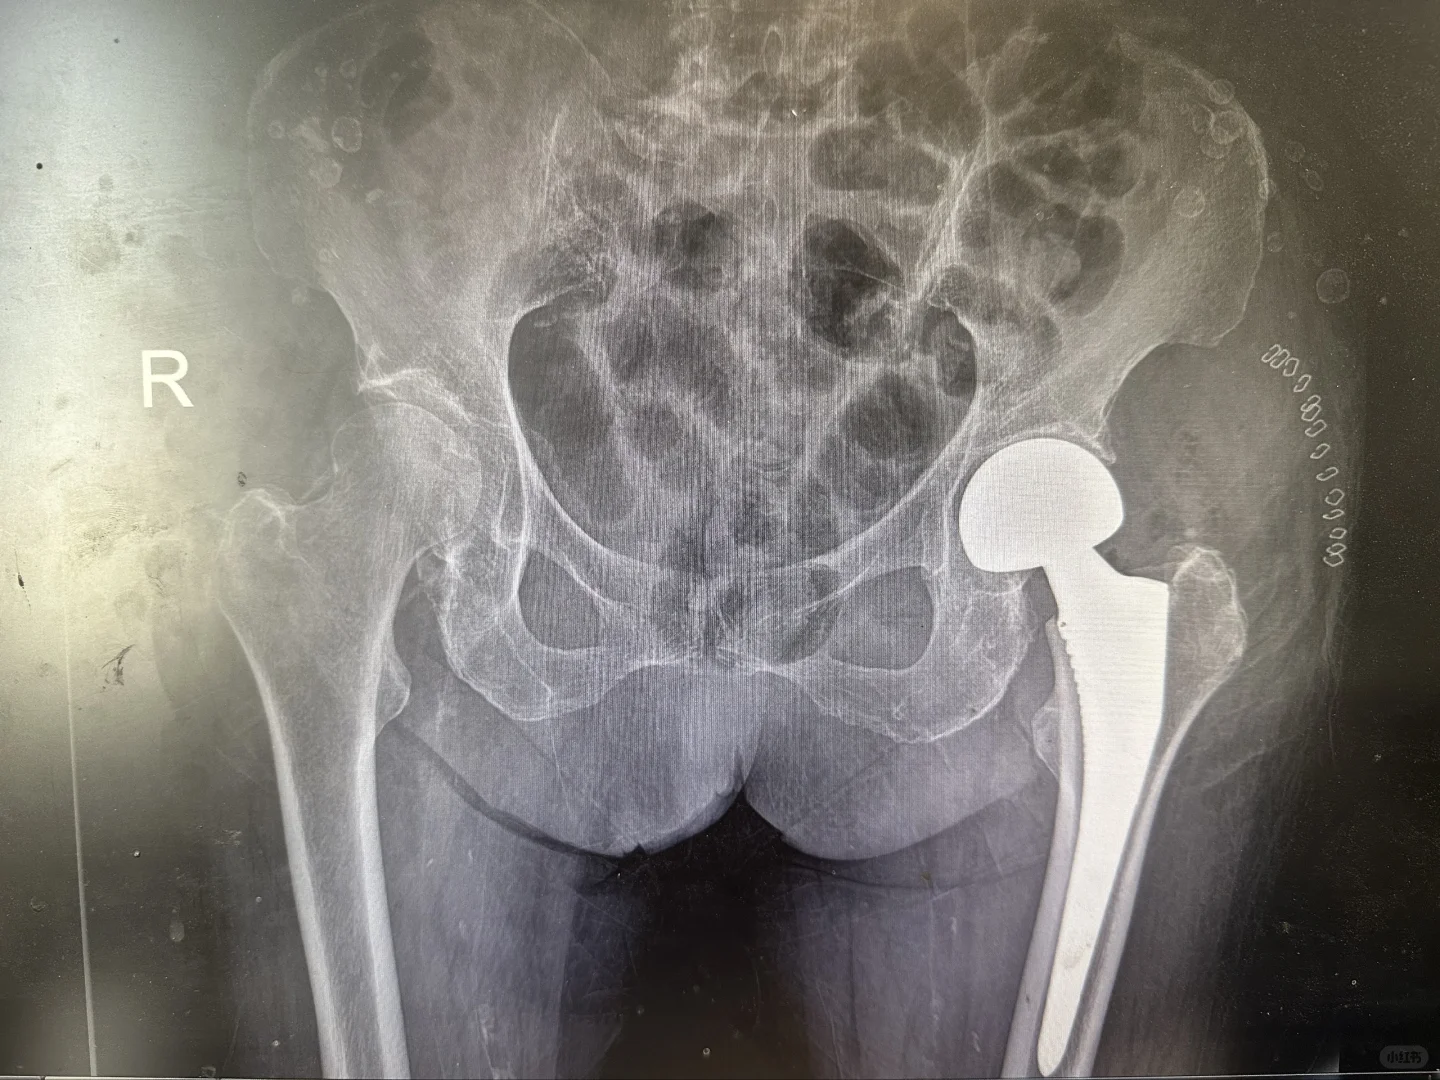

髋膝关节置换手术是二十世纪以来最成熟的手术,1小时的手术时间能够给患者带来关节的重生,从此告别让人无法忍受的疼痛,回归正常生活,老人上下楼梯爬山跳舞不是梦。

给大家看看我们的手术器械和术后影像,抡大锤的马医生在线回复您的疑问,点个关注,持续解答。